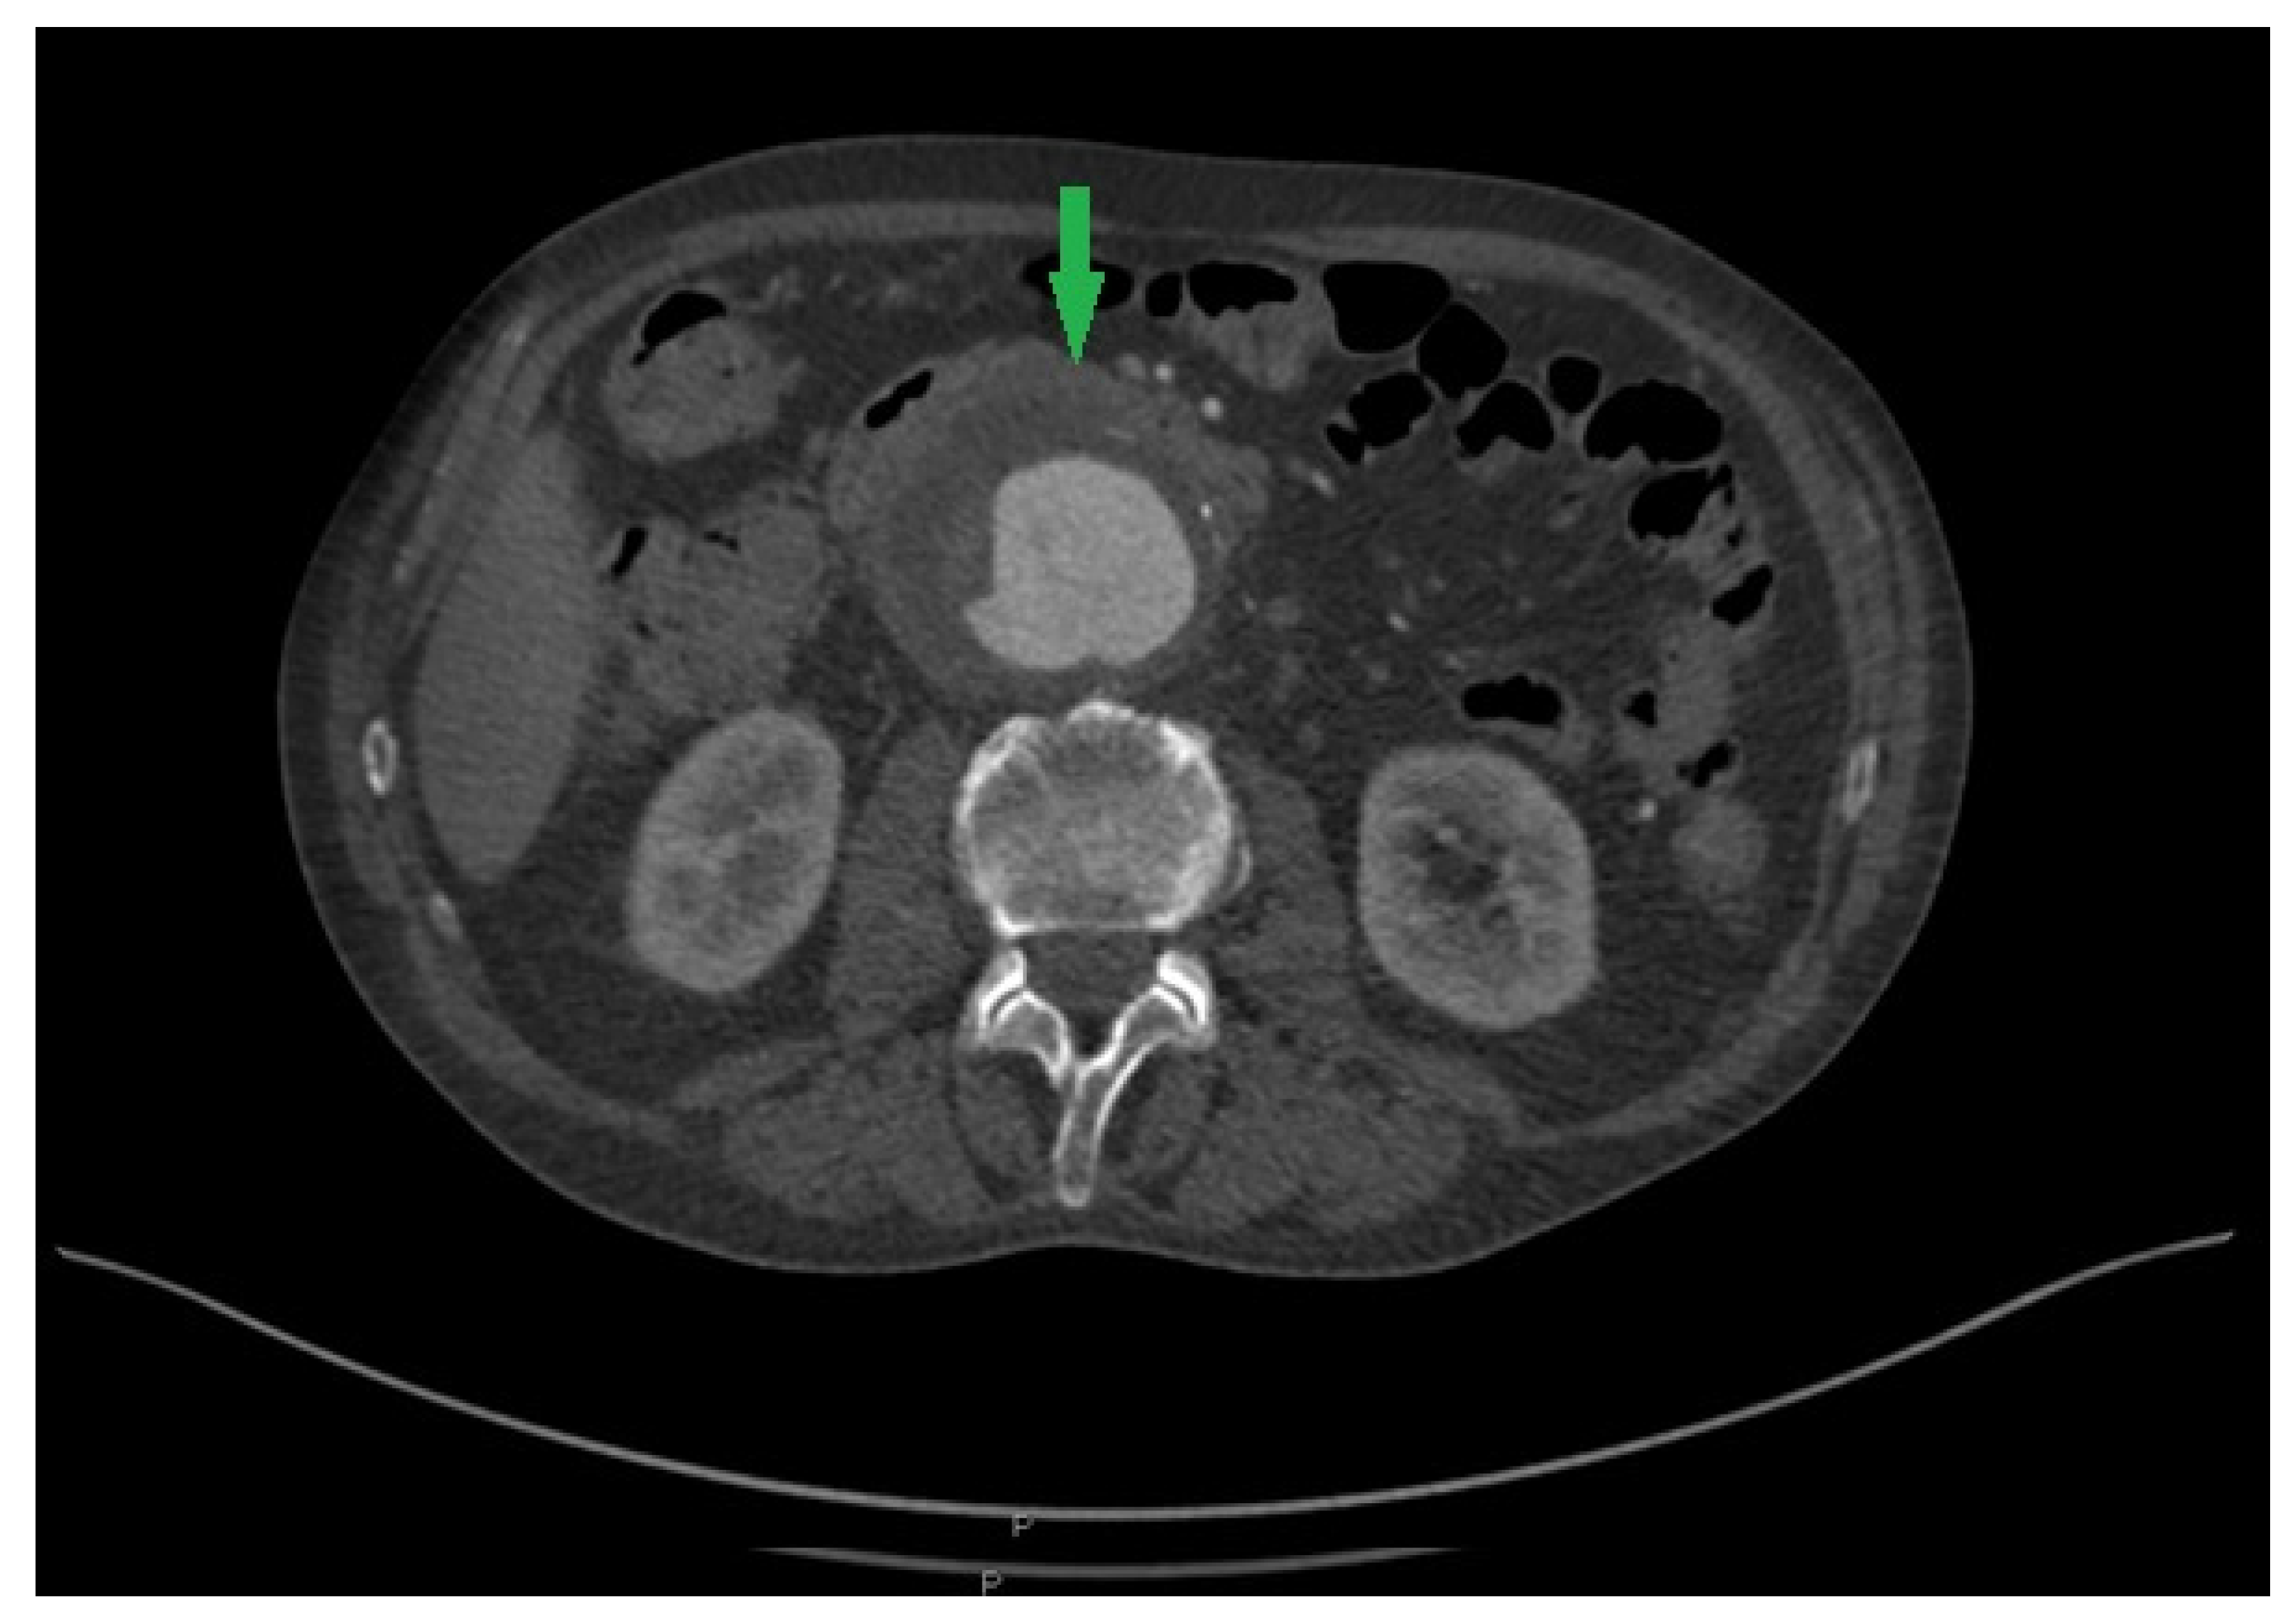

2. Case Report